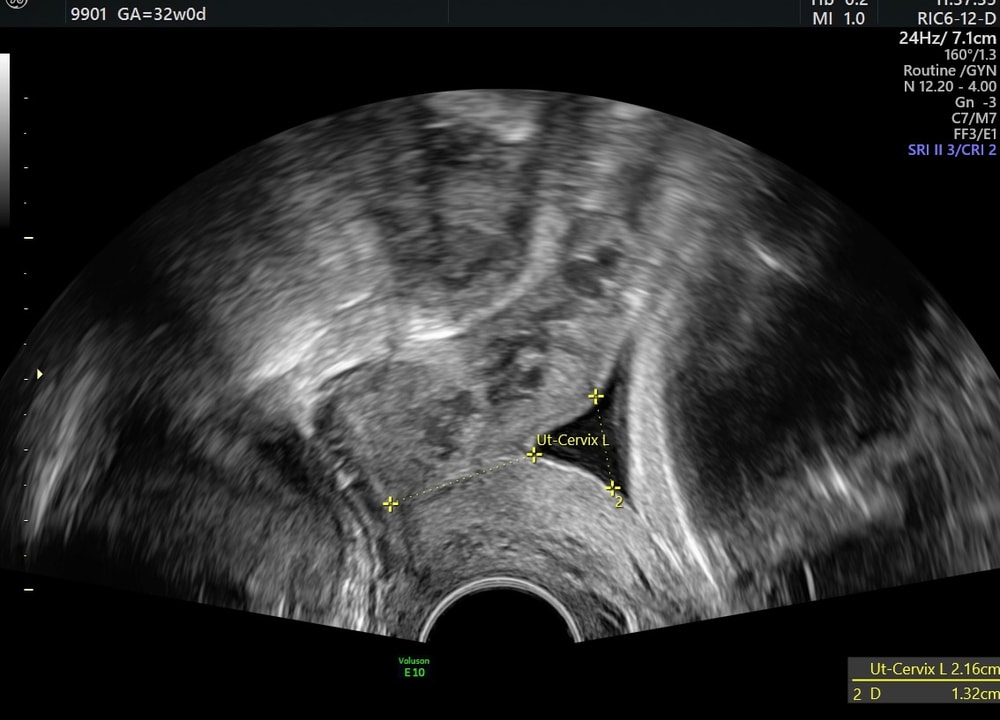

Дарья , нет, укорочение шейки на таком сроке является абсолютно нормальным процессом, у меня всю беременность шейка была от 25 до 28 мм, с 20 недели началось воронкообразное расширение внутреннего зева. Вот нашла снимок ровно в 32 недели, длина шейки 21,6 мм, расширение зева - 13,2 мм, в 34 недели расширение зева такое же, но уже длина шейки 13,9 мм, отошла пробка и шейка пропускала 1 палец, ну в итоге больше 4 недель еще ходила. Изображение